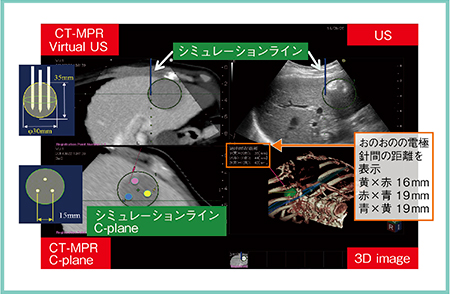

具体的には,超音波画像と同期させたCTやMRIのMPR画像上に複数の電極針穿刺のシミュレーションを可能とし,C-plane画像(穿刺方向と直交する断面)および3D透過画像(3D image)の表示や,各電極針間の距離も表示されるため(図1),電極針相互の位置関係の把握を容易にする。また,同シミュレーション画像と穿刺のシミュレーションラインをナビゲータとして,リアルタイムに電極針の穿刺が可能である。

図1 3D Sim-Navigatorの表示画面

症例1は,70歳,女性。肝S6に3.4cmの肝細胞がんの再発が認められ,肝動脈化学塞栓療法(TACE)併用にてバイポーラ4cm針3本によるRFAを施行した。C-plane画像にて電極針の穿刺位置を正三角形状に設定すると,それがCT-MPR画像(Virtual US),超音波画像および3D image上に黄色,赤,青のラインで表示される(図2)。これにより,電極針相互の位置関係を容易に把握可能であった。治療後のCTでは十分なマージンが確認できた。

図2 症例1:肝細胞がん再発症例へのバイポーラRFA